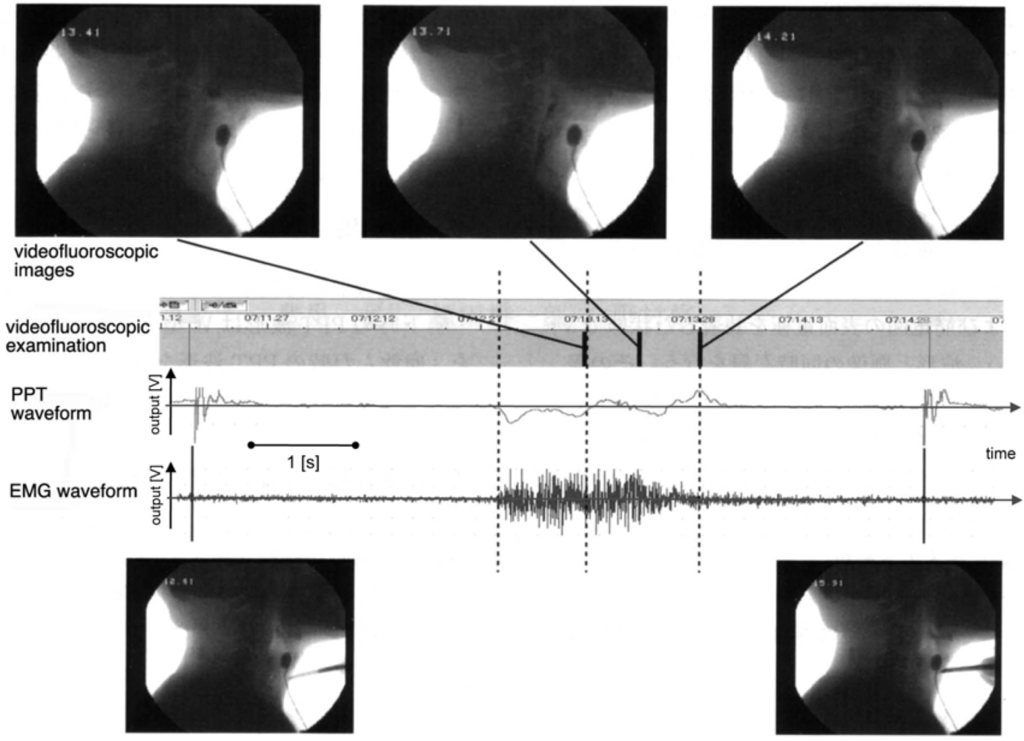

- Toyosato, A.; Nomura, S.; Igarashi, A.; Ii, N.; Nomura, A. A Relation between the Piezo-Electric Pulse Transducer Waveforms and Food Bolus Passage during Pharyngeal Phase. Prosthodont. Res. Pract 2007, 6, 272–275. [Google Scholar]